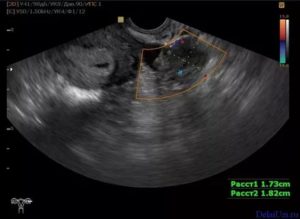

Описание лютеиновой железы на УЗИ:

| Параметры | Эхопризнаки | Как выглядит |

| Внешний вид | Гетерогенное анэхогенное образование | На яичнике округлое темно-серое пятно с черными вкраплениями и единичными белыми точками |

| Структура | Гиперэхогенное образование с крупными зонами низкой плотности (гипо- или анэхогенными очагами) | Серое пятно с большой площадью затемнений. Окрашены черным места скопления крови, локализации сосудов |

| Размер | В норме до 30 мм, при образовании кисты – более 3 см | Диаметр ЖТ сверяют с нормой по фазам желтого тела |

Если диагност выявил два желтых тела или больше, в протоколе УЗИ описывается каждое образование. Растущая и угасающая железа неодинаково выглядит. С началом регрессии она уменьшается, светлеет. Черное пятно без вкраплений – эхопризнак жидкостной кисты.